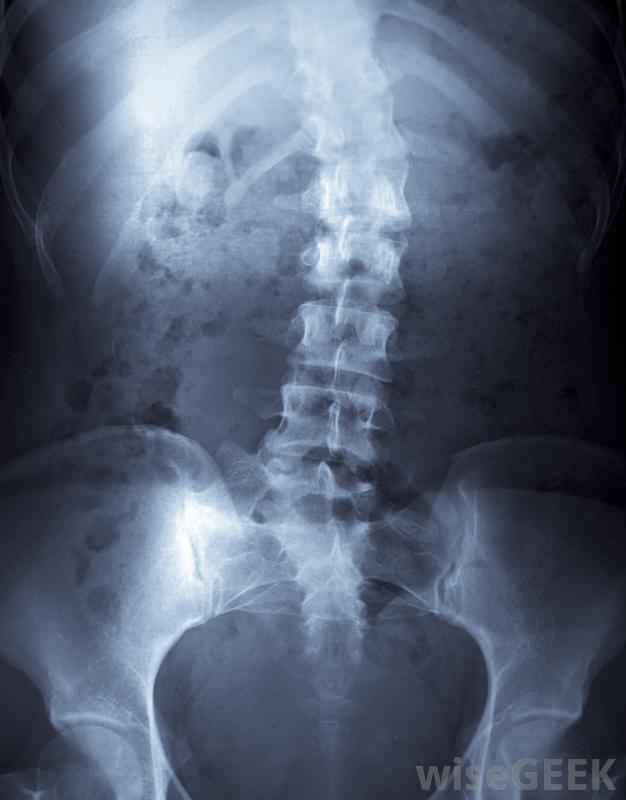

脊柱融合术可用于治疗严重的脊柱侧凸。

两个或两个以上的椎骨在一个称为脊柱融合的医疗程序中连接在一起。